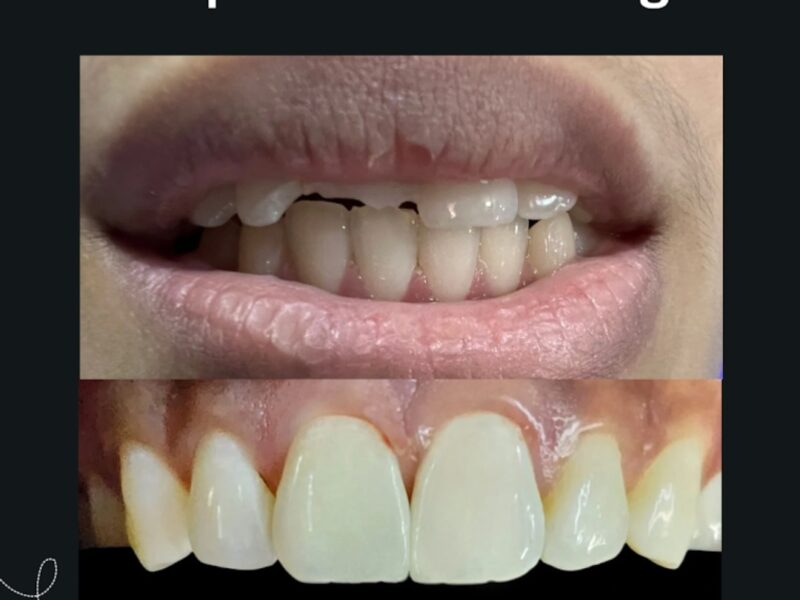

✔️ Cosmetic Smile Makeover

Cosmetic & Aesthetic Dentistry

Teeth Whitening